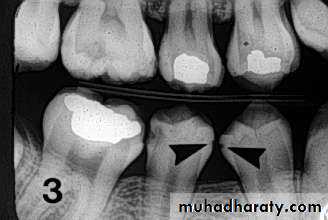

Recurrent cariesIt is diagnosed whenever there is softness due

to caries at a defective margin, and when the tip

of a periodontal probe can enter the defect

without any resistance.

A restoration with a discolored margin or a small

marginal ditch (<0.5 mm or the head of the

probe) is recorded as an early recurrent

carious area. A larger defect should be

classified as advanced recurrent carious area

There are two valid indicators of recurrent (secondary) caries:

• softness at the margin of a filling that is detectedusing an explorer or

• presence of a large defect (a minimum diameter of

0.4 mm) at a margin of a filling with softness in the

area.

Large defects are associated with a high level of colonization with cariogenic bacteria.

Marginal discoloration by itself is not a valid sign for

dental caries.